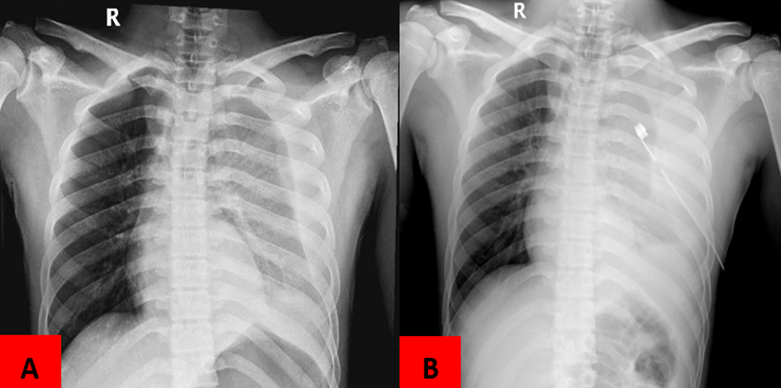

Clearing the breathing through left side of the chest tube thoracostomy resulted in the loss of 300 ml of blood during the procedure. Blood was being produced at a rate of 250 ml per hour prior to entering the operating room. A transurethral catheter was inserted to collect and analyze urine samples. Testing included a complete blood count, blood glucose and a chest X-ray. Hemoglobin levels were low (9.1 g/dL), white blood cell counts were high (18.7 x 103 cells/L) and segmental neutrophil percentage was high (89.2%). The blood gas analysis found (pH \: 7.2, BE: -1.7 mmol/L), (PO2: 76.6 mmHg) and lactate serum increased to 1.9 mmol/L. Chest X-ray examination showed that a massive hemothorax (Figure 2).

Figure 2. Picture A: Chest X-Ray patient before chest tube thoracostomy, Picture, B: Chest X-Ray patient before chest tube thoracostomy